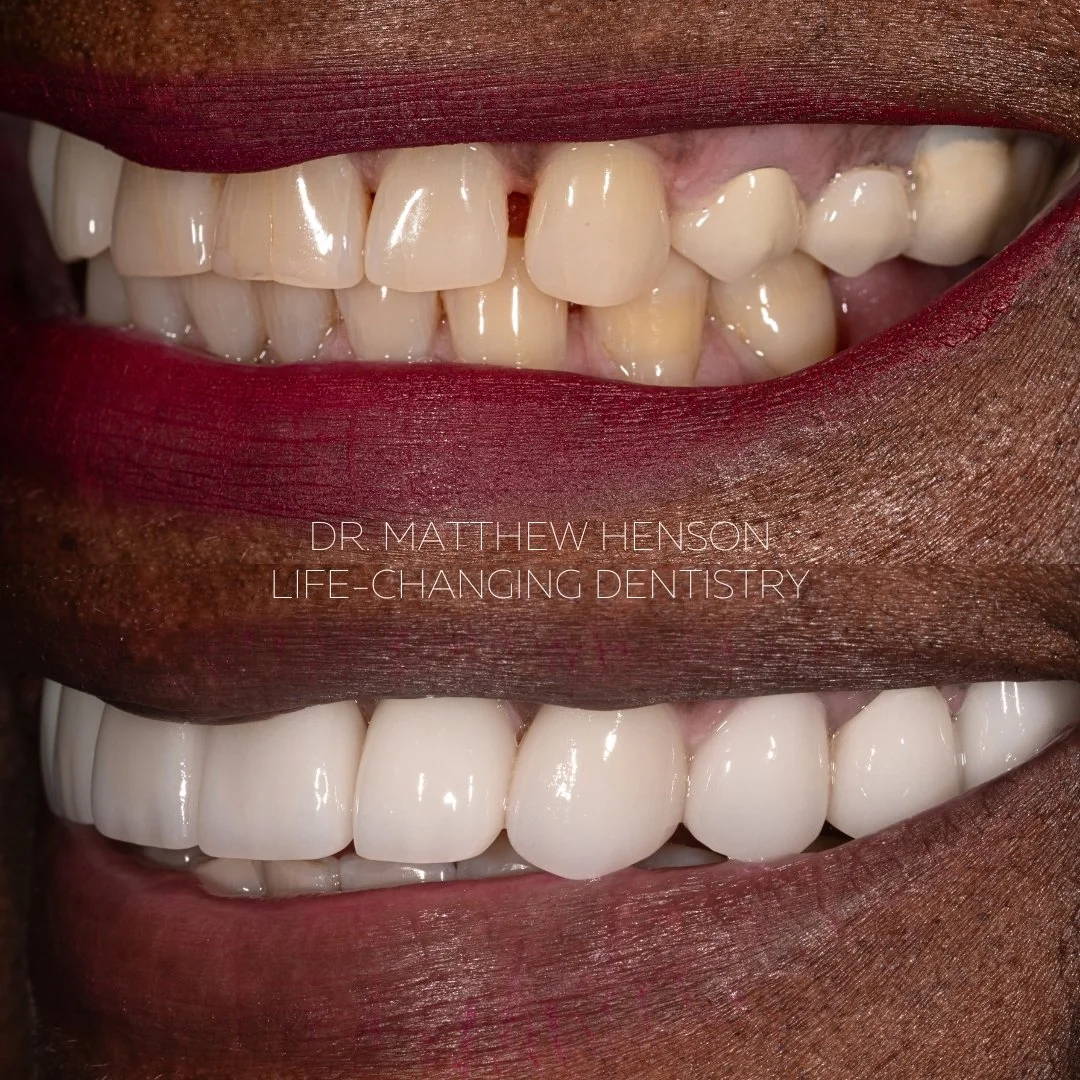

Patient A.N.

Two bridges and 5 veneers to give a more youthful appearance

Patient sent photo of herself from high school saying she wanted her old smile back

Two bridges and 5 veneers to give a more youthful appearance

Patient sent photo of herself from high school saying she wanted her old smile back